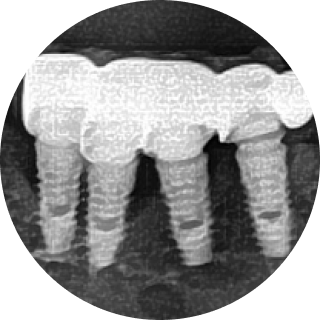

이제는 임플란트 회사, 임플란트 브랜드 선택의 관점에서 벗어나서 임플란트 수술 진단부터 최종 치아 제작까지. 이 모든 과정에서 보철학적 목표를 디지털 방식으로 어떻게 완성해 내는지가 선택의 관점이 되어야 합니다.

이로운 치과는 간단하고 정확하며 안전한 치료를 위한 디지털 진료 방식을 지향합니다.

이로운 치과는 디지털 진료를 통해 정확한 임플란트 식립 위치를 파악하여

아날로그 치료에서 발생할 수 있는 문제를 예방합니다.

디지털임플란트 개인 맟춤 디지털 수술 가이드

디지털임플란트 덴티움 임플란트

디지털임플란트 환자 맞춤형 지대주

디지털임플란트 CAD/CAM 지르코니아 크라운

이 모든 술식, 장비, 소프트웨어 노하우가 집약된

이로운치과의 디지털 임플란트

89만원~

(시술 난이도, 골 이식 등에 따라 비용이 달라질 수 있습니다)